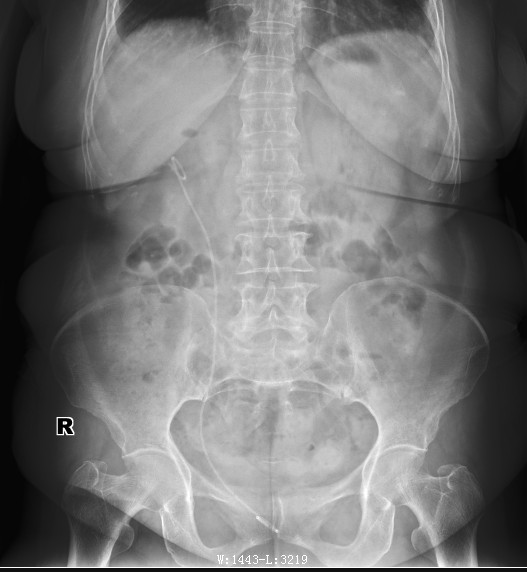

我们看看术后效果

效果基本不错,有极少数残余结石,通过后期活动排石,有可能结石会全部排出体外;术后3-4天出院,极大的解决住院时间长,并术中基本没有创伤;有点很突出;我们再看看今天一例男性患者